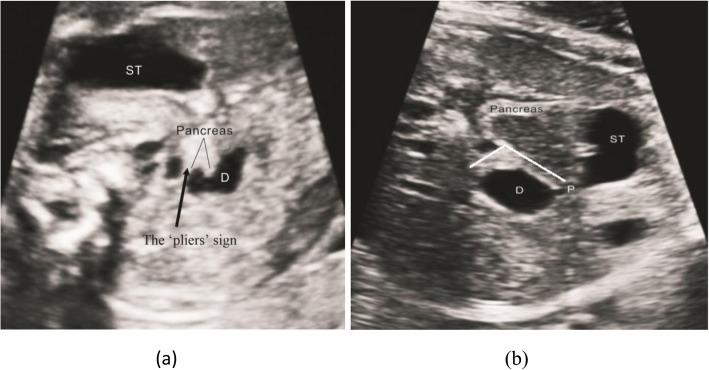

The results showed that there were 17 patients (42.5%) of congenital duodenal diaphragm, all with a 'rat tail' sign on the ultrasound images. Moreover, there were 4 patients (10.0%) of CDO caused by annular pancreas, all with a 'pliers' sign on the ultrasound images. We summarized the imaging features of the 'rat tail' sign and the 'pliers' sign.

CONCLUSION

The main conclusion of this study was that the 'rat tail' sign could be used as an indirect ultrasound feature to diagnose duodenal diaphragm. The 'pliers' sign could be used as a direct ultrasound feature in the diagnosis of annular pancreas in CDO.

结果显示,有 17 例(42.5%)患者为先天性十二指肠隔膜,超声图像均显示“鼠尾征”。此外,有 4 例(10.0%)患者为环状胰腺引起的 CDO,超声图像均显示“钳子征”。我们总结了“鼠尾征”和“钳子征”的影像学特征。

结论

本研究的主要结论是“鼠尾征”可作为间接超声特征用于诊断十二指肠隔膜。“钳子征”可作为 CDO 中环状胰腺的直接超声特征。